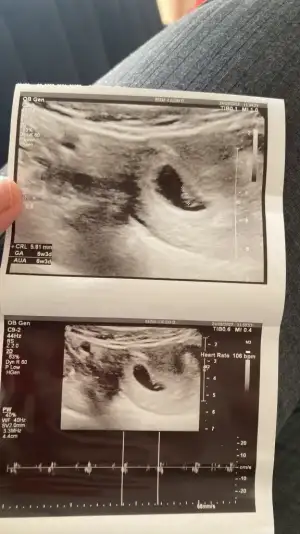

Teşekkür ederim🤗 size de hayırlı olsun geç gitmek en iyisi zaten ama sıkıntılı olunca öğrenir öğrenmez mecbur gidiyorsun beta takibi keseyi görebilecek miyim kalp atışı diye telaş ediyor insan günler geçmek bilmiyor

Bugün gittim henüz kese yok 😞 beta takip edecek sonuç bekliyorum 4+6 hafta çıkıyor regli hesabı ile